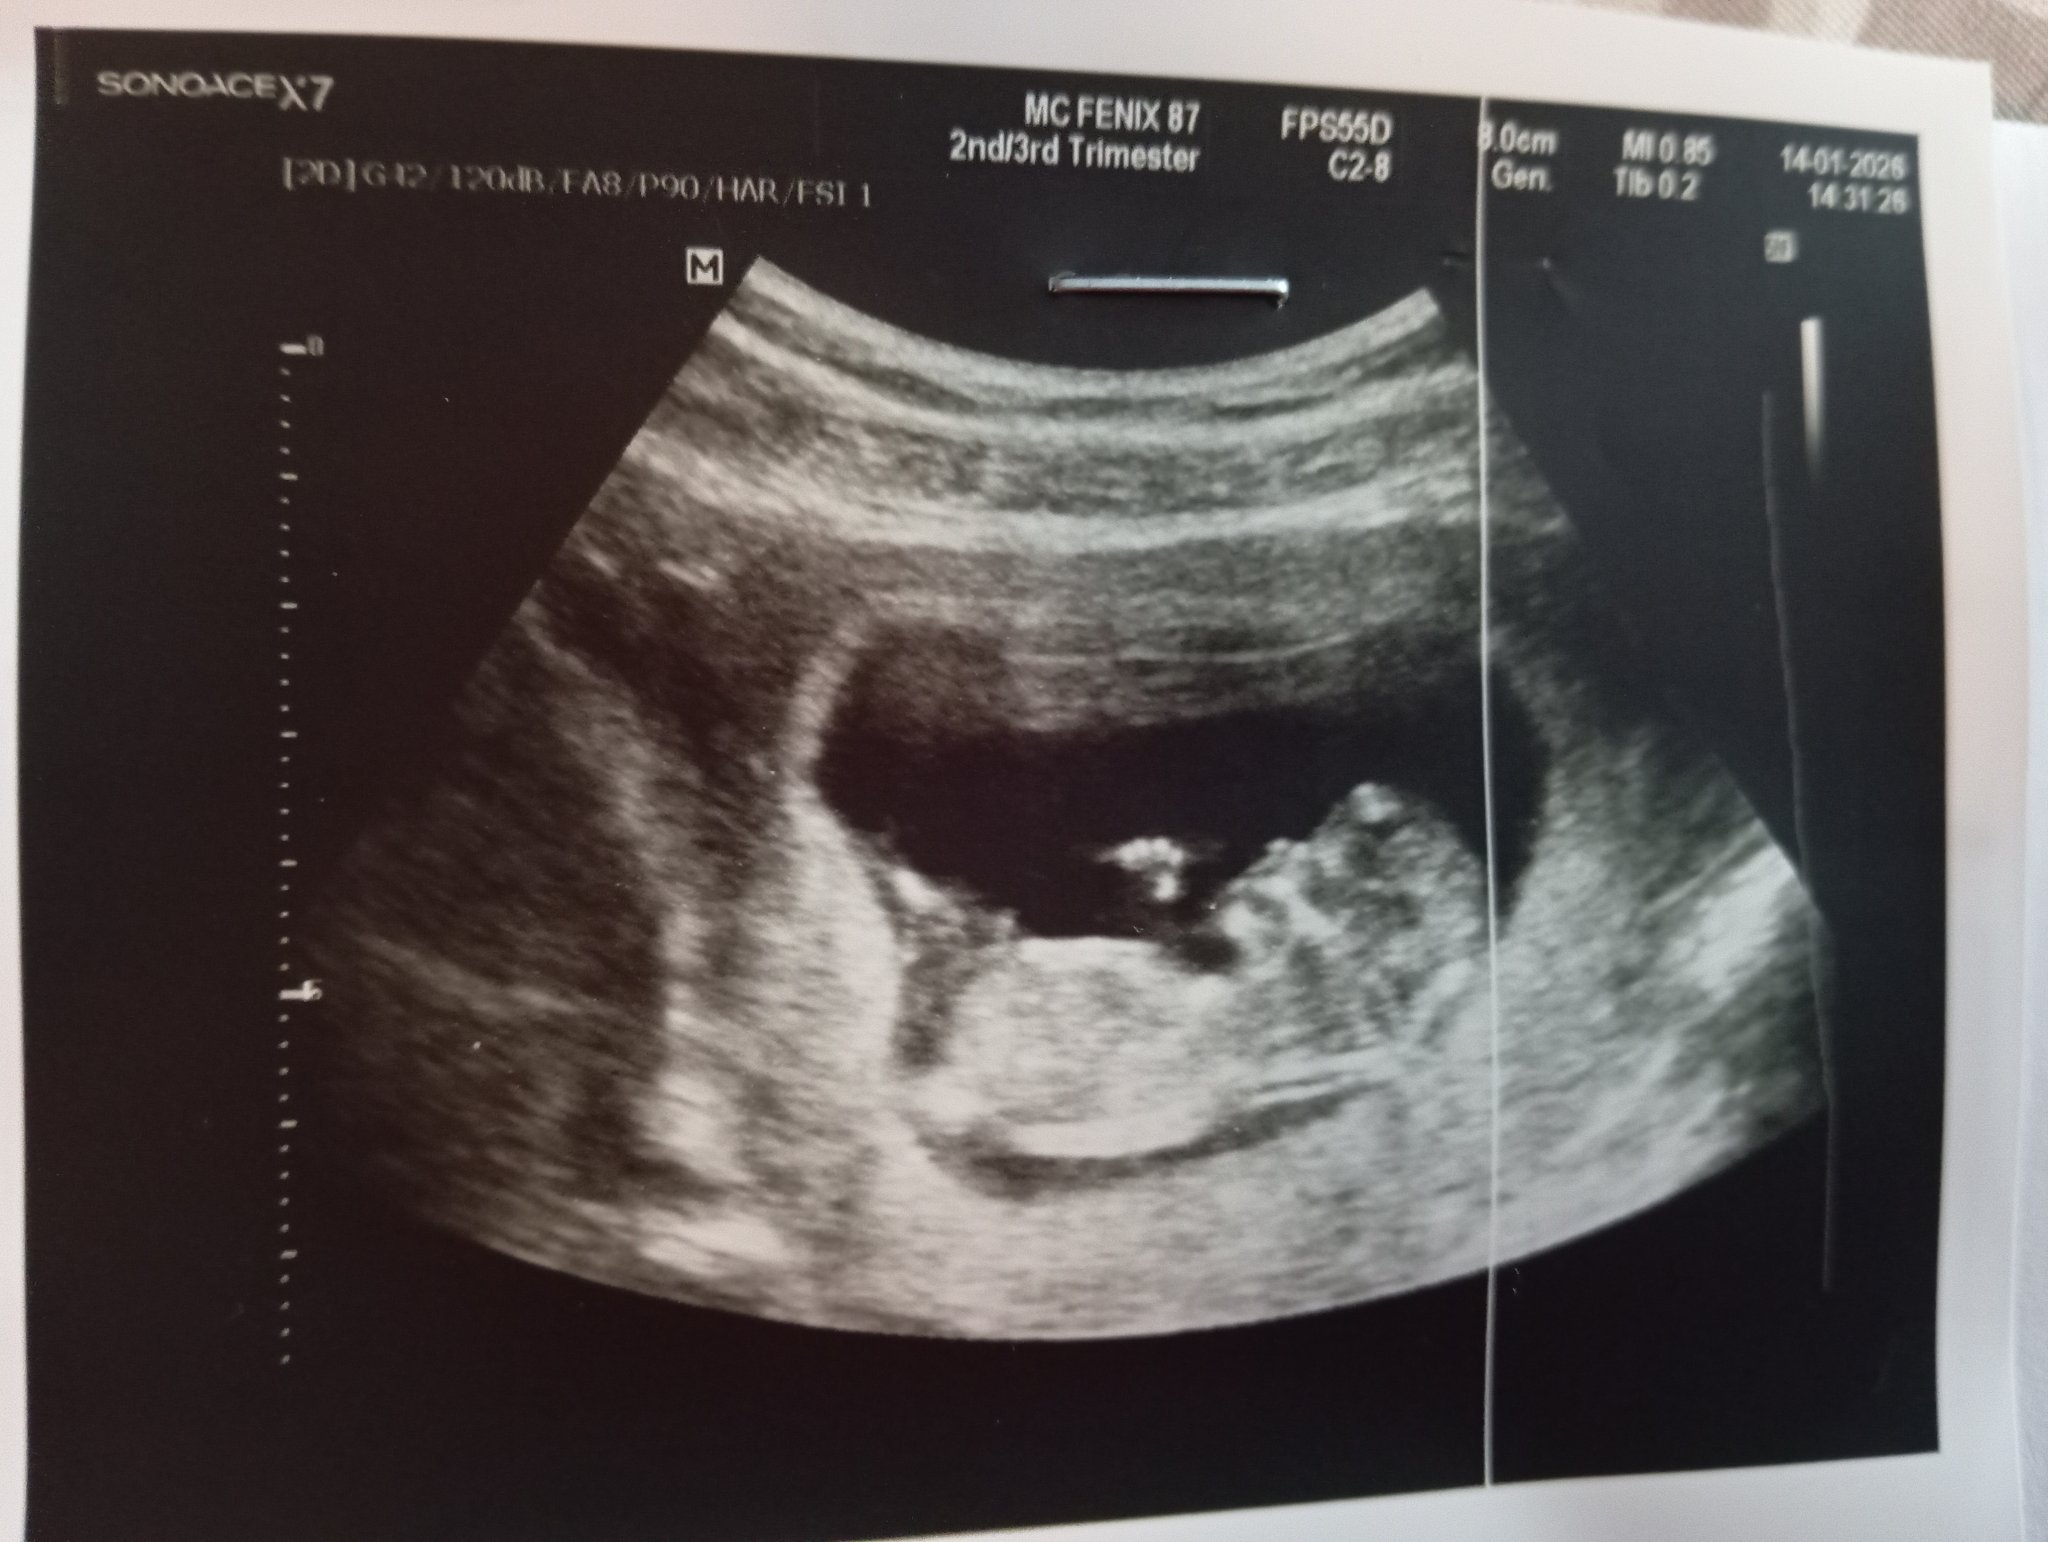

И аз вчера ходих на първа фетална морфология. Бебето не беше много кооперативно, но след но шпа и малко почивка реши да съдейства. Всичко изглежда наред. Пол следващия път.

И при нас вчера много шаваше и даваше да му видим само главата Sweat Smile даже ме накараха да хапна нещо сладко, че да се размърда. През цялото време само мърдаше с ръце, едвам хванахме една свястна снимка. Satisfied